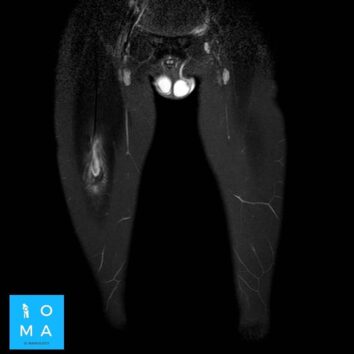

🔹Varón de 12 años que consulta por tumefacción en región anterior de muslo derecho. Refiere molestia a ese nivel 3 días antes, después de pique en partido de fútbol.

🔹Cambios inflamatorios asociado a edema y banda líquida que rodea a la unión miotendinosa central del sector medio del músculo recto anterior del cuádriceps derecho, de 10 mm de extensión, evocador de desgarro de la unión miotendinosa grado II.

🔹En un segundo tiempo se realiza ecografía dirigida, confirmando los hallazgos a nivel del tendón central del músculo recto

anterior del cuádriceps derecho, presentando desgarro grado II, asociado a un

aumento del flujo vascular al examen Power doppler.